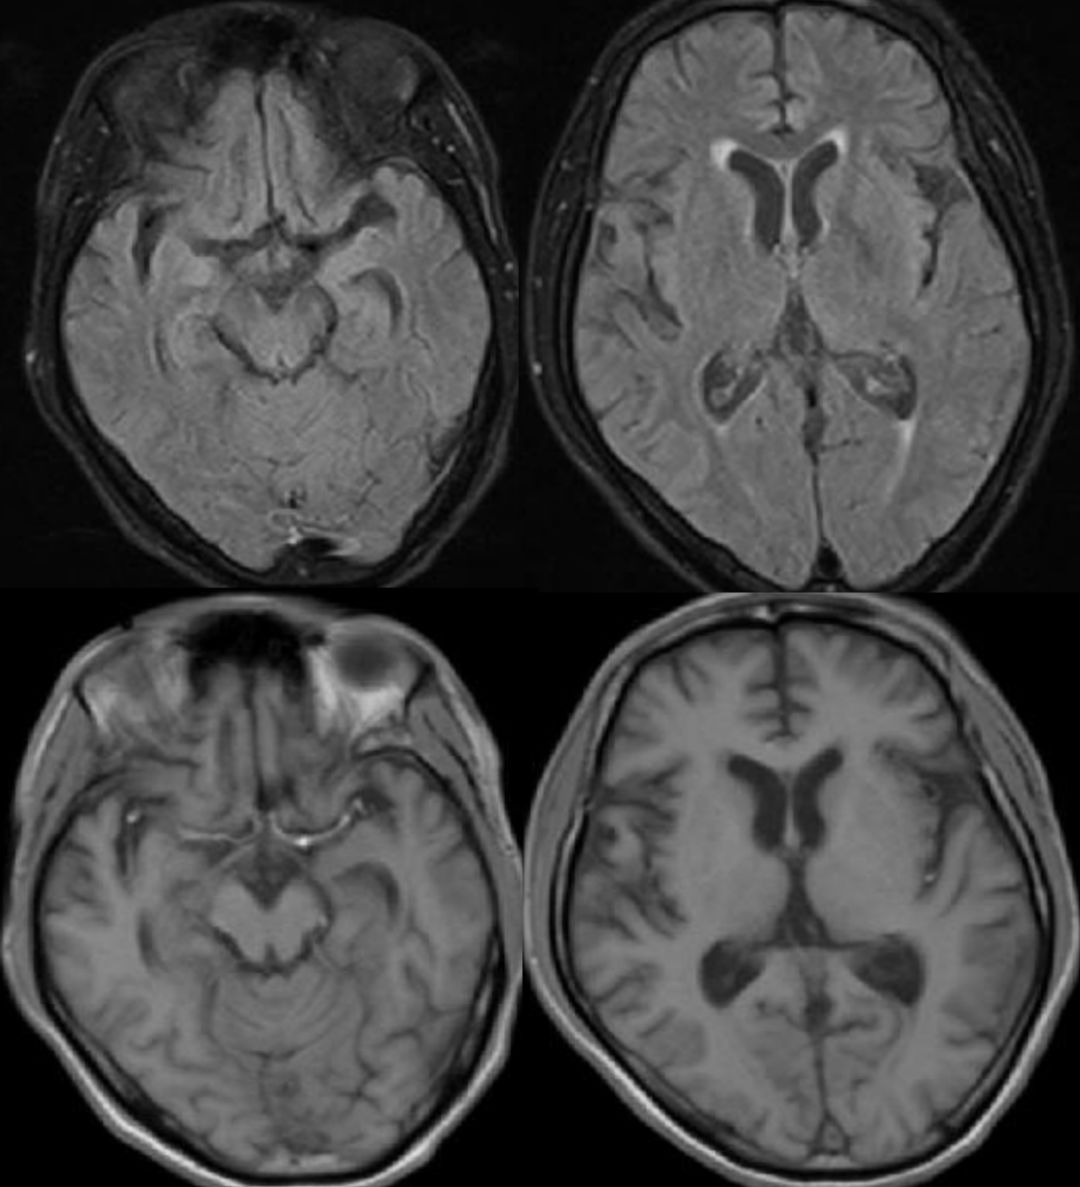

患者,21岁女性,患者3小时前做某手术后突 发右侧肢体乏力、意识不清。

发病24小时磁共振:

答案:脑型脂肪栓塞综合征。患者做了自体脂肪填充术。脂肪栓塞综合征(fat embolism syndrom,FES)是指直径为10~40μm的血管内脂肪颗粒阻塞血管腔而引起的一系列病理生理改变的临床综合征。FES常发生于骨创伤及骨手术病人。FES潜伏期为6~24h,FES 的典型三联征为低氧血症、意识障碍和瘀斑。